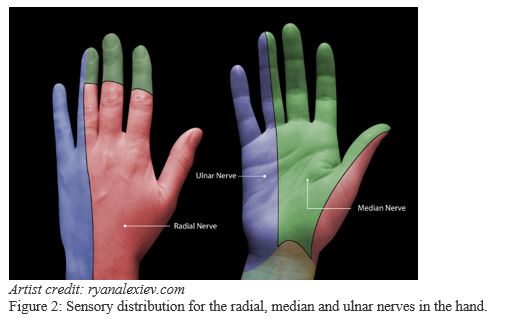

2. Know the sensory distribution of each nerve (Figure 2)

Decide on either a partial or complete block of the hand.

For major hand injury:

- Block the radial, median and ulnar nerves (complete hand block)

For injury to thumb, index, middle and ring fingers or for injury to palmar or dorsal hand not on ulnar aspect:

- Block the radial and median nerves

For boxer’s fracture, injury to ulnar hand or little finger:

- Block the ulnar nerve